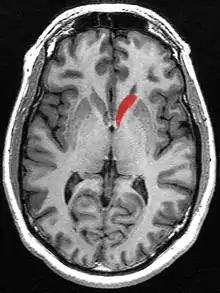

![]() Caudate nucleus (in red) shown within the brain | |

Transverse Cut of Brain (Horizontal Section), basal ganglia is blue | |